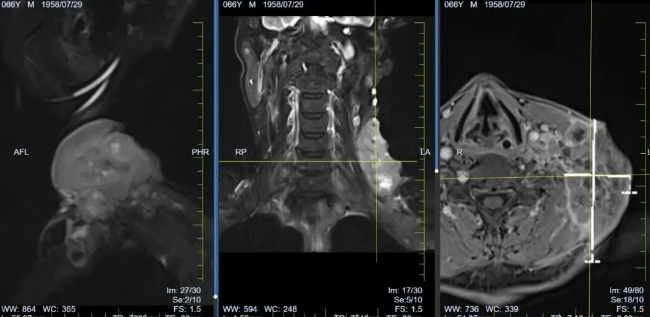

*患者颈部肿块治疗前

“刚开始还担心治疗副作用,没想到医护人员早有准备。” 李先生说,治疗期间出现的轻微恶心、乏力,都在医护团队的针对性护理下得到缓解。更让他惊喜的是,开始治疗后,颈部肿块开始迅速缩小,治疗6个月结束复查时,影像学检查显示,原本 8×10cm 的肿块已完全消失,食管梗阻症状也明显减轻。

*患者颈部肿块治疗后